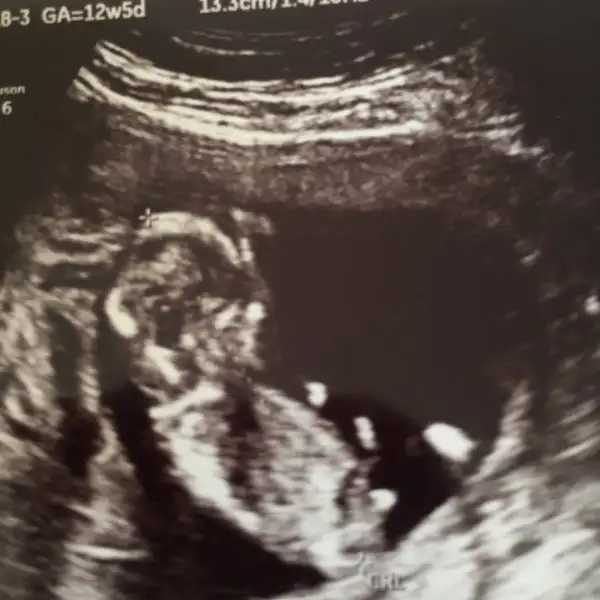

Canım bence bebeğin erkek benimde 13. Haftada bebeğimin usg resmi aynı seninki ile çıkıntısı baya belirgin doktor erkek demişti erkek gerçekten bak buda benim usg resmi

Ay evet ne kadar belli seninkinde de çıkıntı

Kız ve erkek organı birbirine benzermiş yA 12 haftalık dönemde o yüzden acaba mı diye düşündüm bide sanırım şimdi ki bebiş solumda oğlum sağımdaydı